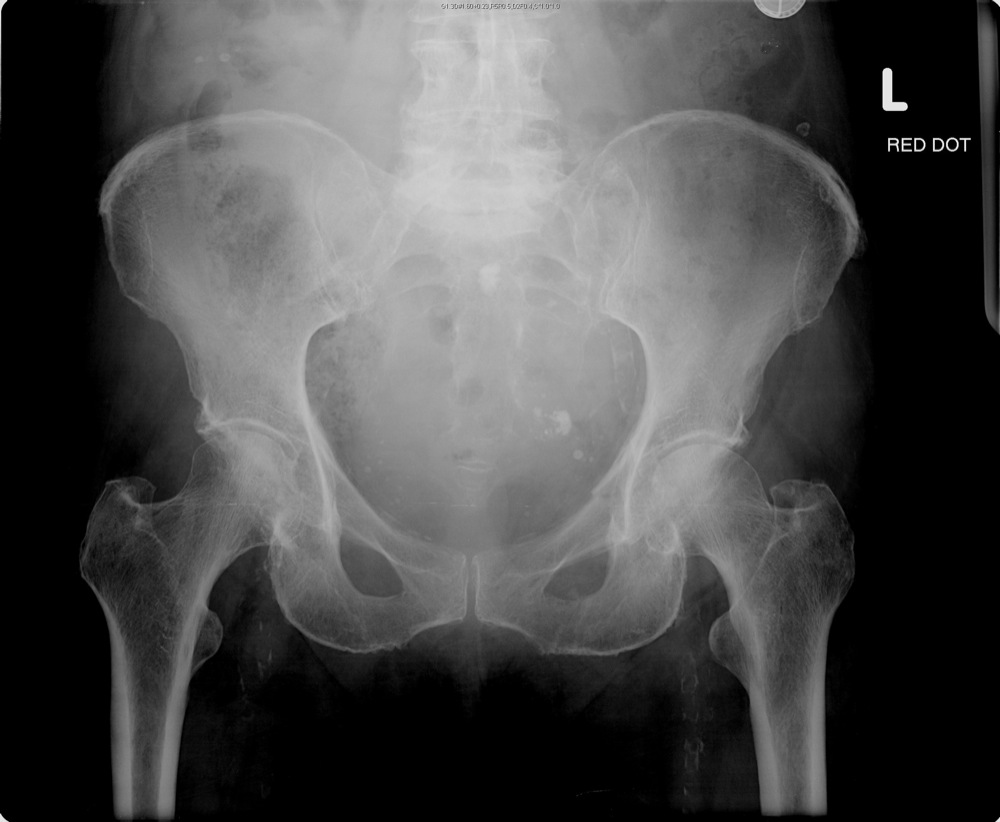

From wikimsk.org

Apophysitis of the Pelvis and Hip WikiMSK What Is Spinal Enthesopathy Lumbar Region Tendons are the tissues that attach your muscles to your bones. Ligaments are what attach your. the lumbar region of the spine, commonly known as the lower back, consists of five vertebrae labeled l1 through l5 and is. enthesopathy may involve any area of the body, but it is most common in the heel, spine, hip, elbow, and. What Is Spinal Enthesopathy Lumbar Region.